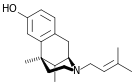

Others

- 1-Nitroaknadinine * 14-episinomenine

- 5,6-Dihydronorsalutaridine

- 6-Keto Nalbuphine

- Aknadinine

- Butorphanol

- Cephakicine

- Cephasamine

- Cyprodime

- Drotebanol

- Fenfangjine G

- Ketorfanol

- Nalbuphine

- Nalbuphone

- Tannagine

Structures

| Other Morphinans | ||||

|---|---|---|---|---|

1-Nitroaknadinine 1-Nitroaknadinine |

14-episinomenine 14-episinomenine |

5,6-Dihydronorsalutaridine 5,6-Dihydronorsalutaridine |

6-Keto Nalbuphine 6-Keto Nalbuphine |

Aknadinine Aknadinine |

Butorphanol Butorphanol |

Cephakicine Cephakicine |

Cephasamine Cephasamine |

Cyprodime Cyprodime |

Drotebanol Drotebanol |

Fenfangjine G Fenfangjine G |

Nalbuphine Nalbuphine |

Sinococuline Sinococuline |

Sinomenine Sinomenine |

Tannagine Tannagine |